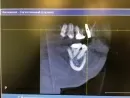

По представленным Вами кадрам складывается впечатление, что верхушка импланта находится в просвете гайморовой пазухи.

Для более точного изучения лучше, конечно, само исследование, в виде файла, который выдают обычно на руки в записанном на диске виде.